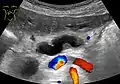

- Ultrasonography of a dilated pancreatic duct (in this case 9mm) due to pancreatic cancer.

Compression, obstruction or inflammation of the pancreatic duct may lead to acute pancreatitis. The most common cause for obstruction is the presence of gallstones in the common bile duct, a condition called choledocholithiasis. Obstruction can also be due to duodenal inflammation in Crohn's disease.[7] A gallstone may get lodged in the constricted distal end of the ampulla of Vater, where it blocks the flow of both bile and pancreatic juice into the duodenum. Bile backing up into the pancreatic duct may initiate pancreatitis.[8] The pancreatic duct is generally regarded as abnormally enlarged if being over 3 mm in the head and 2 mm in the body or tail on CT scan.[9] Pancreatic duct or parts of pancreatic duct can be demonstrated on ultrasound in 75 to 85% of people.[10]